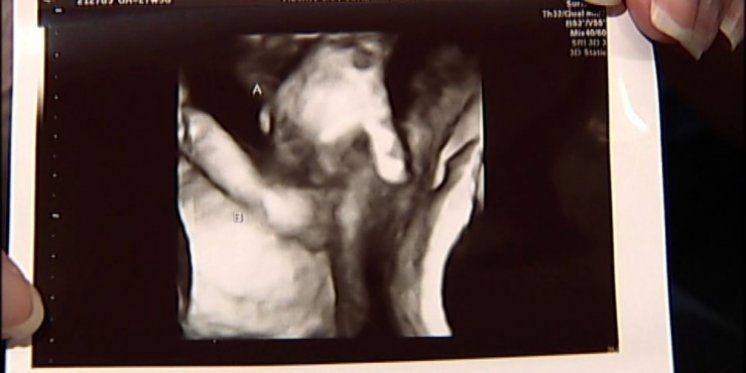

Tijekom ultrazvuka, roditelji su vidjeli nešto neočekivano - dječakovu malenu ruku kako drži prst svoje sestre.

Ona je sačuvala fotografiju sa ultrazvuka, koja će joj, kako kaže, u budućnosti služiti kao dokaz da su se njena djeca neizmjerno voljela.